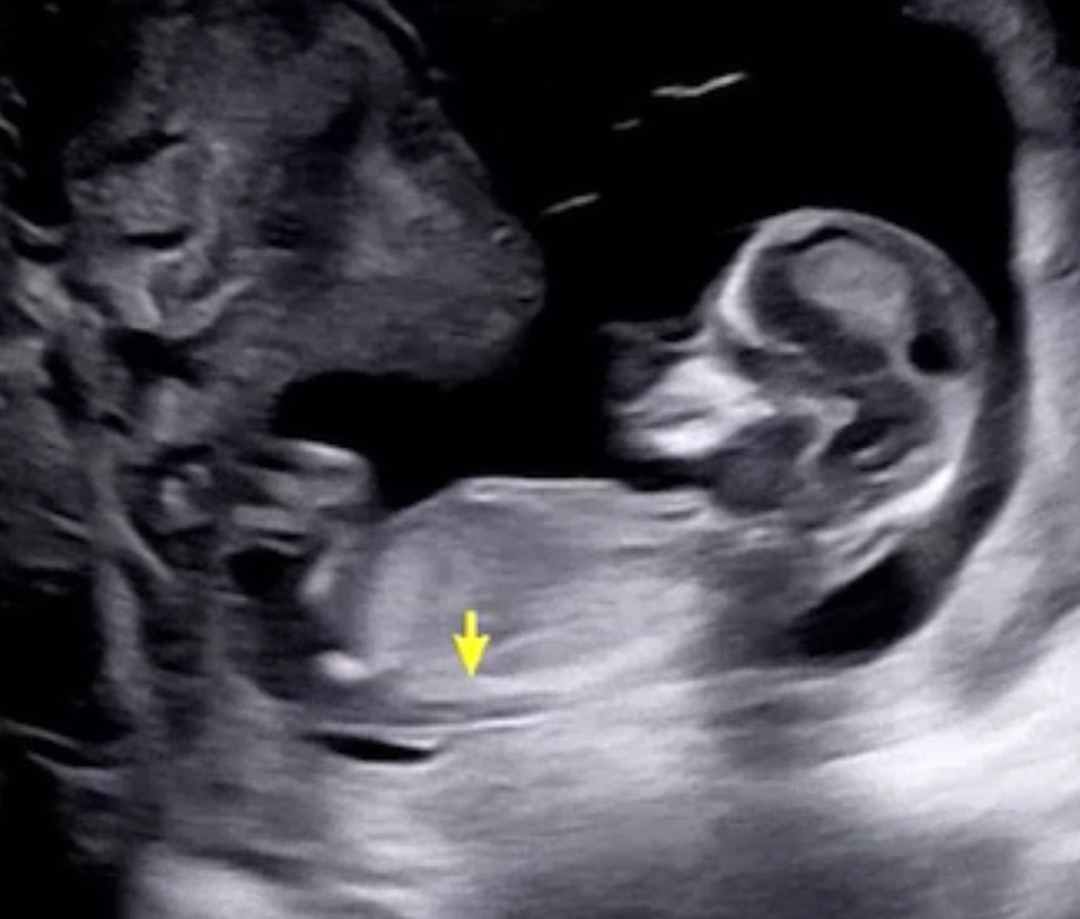

12주 일차기형아검사했어요!

12/4일차 일차기형아검사했는데 일주일만에 만난 홈런이는 또 많이컸더라구요 다행히 코뼈랑 투명대 정상이라해서 한숨돌립니다😭 건강만 하면된다만.. 성별이 점점 궁금해지네요 혹쉬 고수님들 각도로 알수있을까요 ㅎㅎ